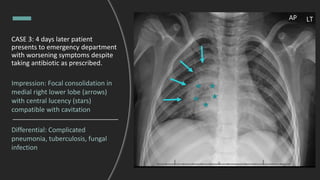

CASE 3: 4 days later patient

presents to emergency department

with worsening symptoms despite

taking antibiotic as prescribed.

Impression: Focal consolidation in

medial right lower lobe (arrows)

with central lucency (stars)

compatible with cavitation

Differential: Complicated

pneumonia, tuberculosis, fungal

infection